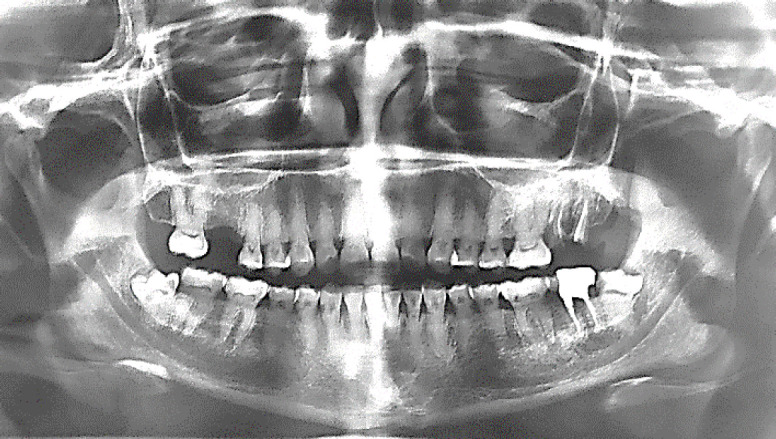

Dentin Dysplasia Type II (DD-II) is a rare genetic disorder that affects the coronal dentin, often leading to pulp stones and complicated endodontic treatment. This case report presents the endodontic management of DD-II in an 11-year-old female patient. The patient, referred for root canal treatment, exhibited symptoms of moderate pain and was diagnosed with pulp necrosis in tooth #19; radiographic findings revealed multiple pulp stones, pulp canal calcification, and apical radiolucency. Endodontic treatment was performed, involving the removal of pulp stones with ultrasonic tips, careful cleaning and shaping of the root canals, and obturation using gutta-percha and AH-26 sealer. Twelve months post-treatment, the patient showed complete healing of the apical lesion, with no related complications. This case underscores the importance of early diagnosis and timely endodontic intervention for favorable outcomes in patients with DD-II.